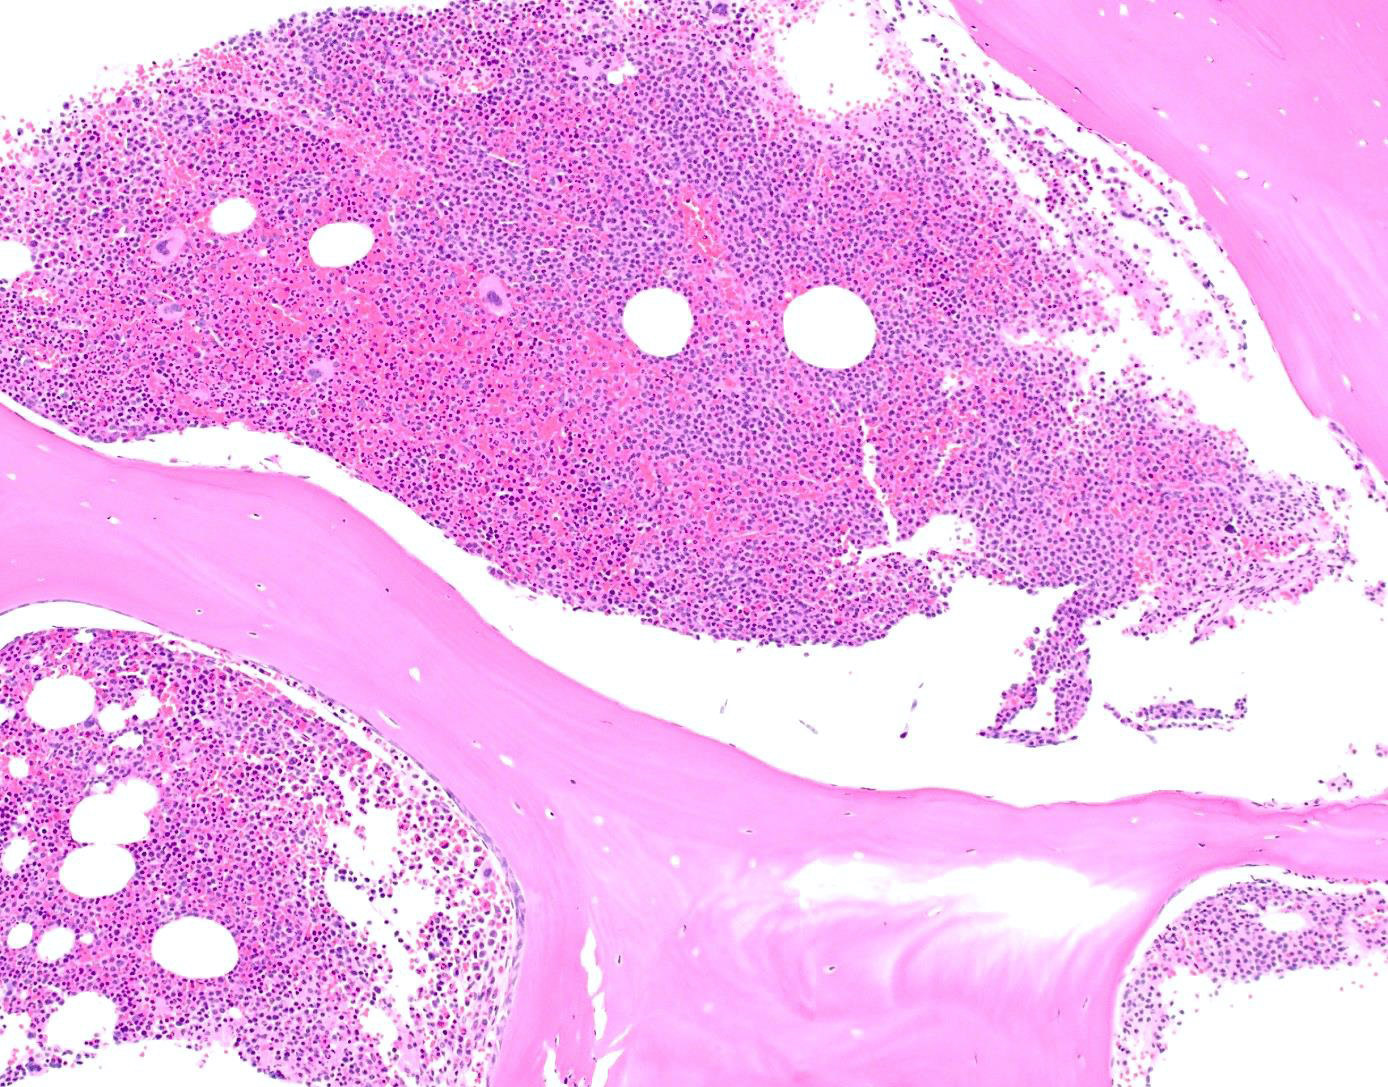

Microscopic (histologic) description

- Core biopsy (Am J Clin Path 1987;87:342):

- Interstitial clusters, nodules or sheets of plasma cells

- Areas of bone marrow may be spared with preserved hematopoiesis, other cases may have diffuse involvement and markedly suppressed hematopoiesis

- Prominent osteoclastic activity may be seen

- IHC to quantify plasma cells (CD138), stains for Ig kappa and lambda to establish clonality

Microscopic (histologic) images

Contributed by Genevieve M. Crane, M.D., Ph.D. and Tapan Bhavsar, M.D., Ph.D.